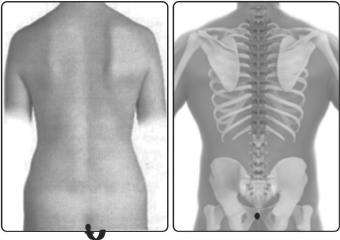

பூவல் வர்மம் மூலத்தின் கடைசி எல்முனையின் அடியில் அமைந்துள்ளது. இவ்வர்மம் மூலவர்மம், கண்கலங்கி வர்மம் என்னும் வேறுபெயர்களாலும் வழங்கப்படுகிறது.

உடலின் முதுகுத்தண்டில் தாழே உள்ள எலும்பின் குமிழினகம் பற்றி பூவல்வர்மம் உள்ளது. இந்த வர்மத்தில் அனல்நாடி எனப்படும் சுழிமுனை நாடி பற்றி தாக்கம் கொண்டால், மது அருந்தியவர்கள் போல் ஆகி கண்கள் திறந்து, முழுமையாய், பார்க்கமுடியாமல் அடைத்து அடைத்து திறக்கும். கால்கள் ரண்டும் நடுக்கமுற்று தள்ளாடும். இதுவே பூவல் வர்மமாகும்.